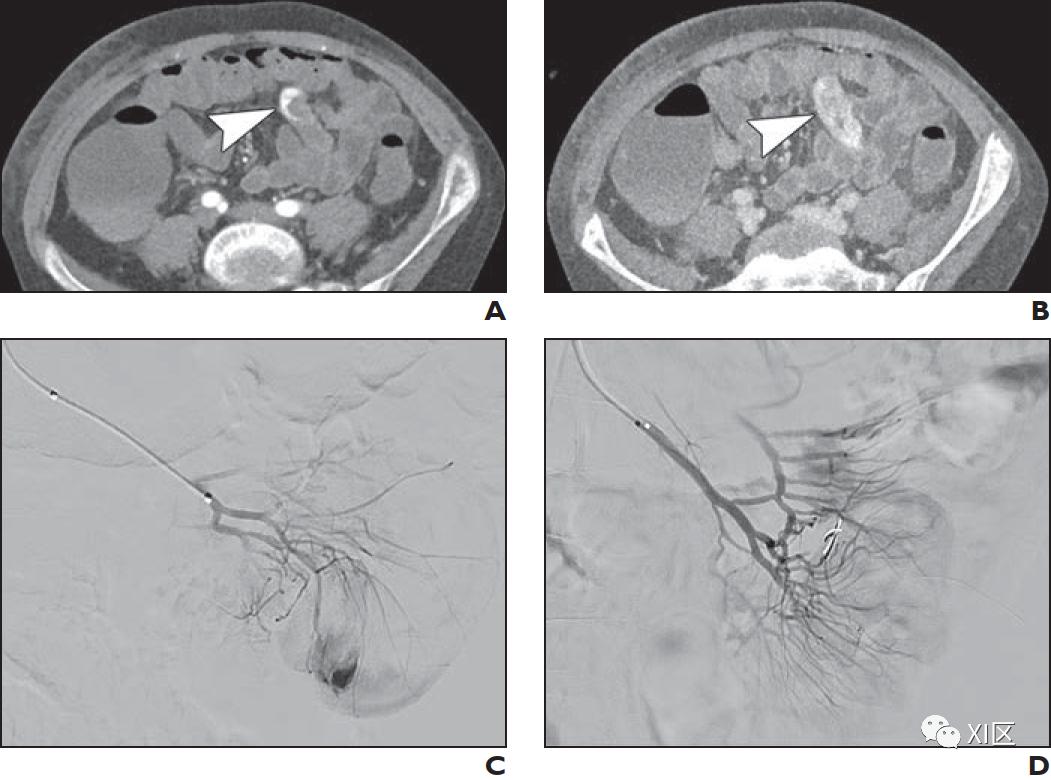

动脉期CTA的轴位成像是描述CPAM和BPS以及手术计划的首选方法(图1)。CTA很容易显示肺的异常部分,包括任何肉眼可见的囊肿。CTA显示供血动脉的位置;通过适当的CTA给药时间,还可以进一步确定静脉引流情况。虽然产后超声可以成功地识别供血动脉,但它高度依赖于操作者,在解剖定位和特征描述方面不如CT。传统导管血管造影曾经是金标准,但由于其具有侵袭性,现在很少使用。

虽然血液动力学不稳定的大咯血患者可能需要通过支气管镜或手术立即治疗,但在稳定的患者中,影像学通常用于确定出血的部位和潜在原因。CTA在63–100%的病例中被反复验证可以定位出血部位。很少在气道中检测到渗出的造影剂。然而,活动性出血的位置可以通过支气管内的液体密度物质或代表肺泡内出血的毛玻璃实变来确定。CTA还可以识别其他潜在的肺实质异常、感染或肿块。也许最重要的是,CTA可以识别异常的肺血管系统,并为计划外科干预或经皮导管栓塞提供路线图(图2)。理想情况下是进行真正的系统动脉期成像,因为支气管动脉来自降主动脉。最大强度投影(MIP)图像增强了支气管动脉和异常血管结构的清晰度。薄层图像能更好地显示小血管结构。